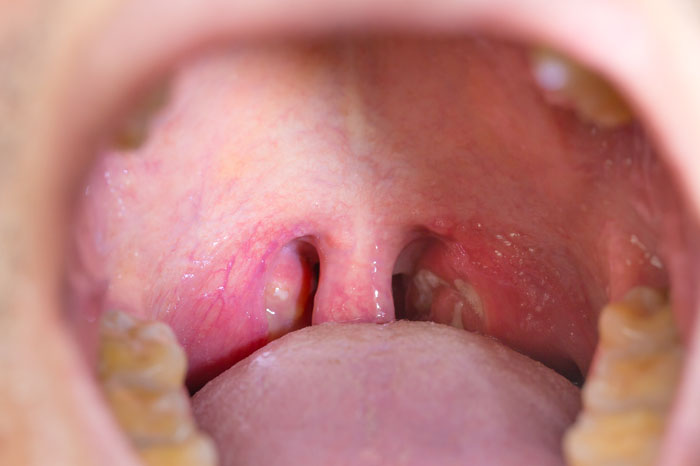

Para que sirven las amigdalas. Las amígdalas son ganglios linfáticos que se encuentran en la parte posterior de la boca y en la parte de arriba de la garganta. Las amígdalas también conocidas como tonsilas son dos acumulaciones de tejido linfoide ubicadas en la parte posterior de la garganta a ambos lados de la faringe. Las amígdalas son ganglios linfáticos que se encuentran en la parte posterior de la boca y en la parte de arriba de la garganta.

PARA QUUE SIRVEN LAS AMIGDALAS. Las amígdalas tienen como función principal la producción de anticuerpos para combatir microrganismos causantes de enfermedades por lo que forman parte del sistema inmunológico.

Las citas especiales son emitidas únicamente por un médico teniendo en cuenta las características y la condición del paciente. Las amígdalas tienen como función principal la producción de anticuerpos para combatir microrganismos causantes de enfermedades por lo que forman parte del sistema inmunológico. Ayudan a eliminar las bacterias y otros microrganismos paraprevenir infecciones en el cuerpo. Una infección viral o bacteriana puede causar amigdalitis. 03012017 Son un grupo de tejidos linfoides que se localizan en destinas regiones de la faringe entre ellos se destacan las llamadas amígdalas palatinascomúnmente llamadas amígdalas y las adenoides también conocidas como amígdalas faríngeas o vegetaciones. Para qué sirven las amígdalas y los adenoides. Algunas personas se preguntan para qué sirven las amígdalas y qué ocurriría si se las retiran.